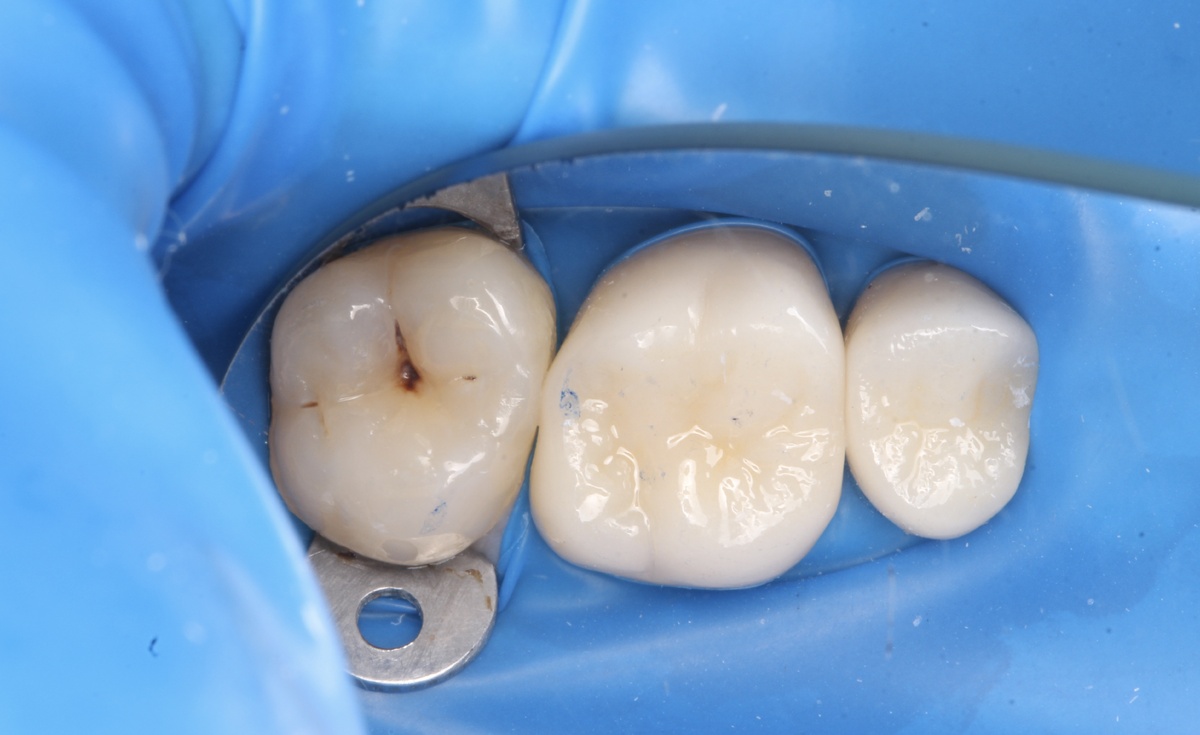

Как лечили: технология имеет значение

Шаг 1: Работа под коффердамом

Это не "причуда перфекциониста". Коффердам — это международный стандарт качественного лечения. Он:

• Изолирует зуб от слюны и бактерий на 100%

• Обеспечивает сухую рабочую зону

• Гарантирует надёжное сцепление пломбы с тканями зуба

• Защищает вас от проглатывания материалов

Без коффердама качественное восстановление контакта невозможно.

Шаг 2: Раскрытие контактной зоны

Работа ювелирная. Нужно:

• Получить доступ к поражённой области

• Не повредить соседний зуб

• Сохранить все здоровые ткани

Для этого используем специальные тонкие боры и работаем под увеличением.

Шаг 3: Удаление кариеса

Убираем только поражённые ткани. Современные индикаторы кариеса помогают видеть границу между больным и здоровым.

Шаг 4: Формирование правильного контакта

Самый важный этап. Здесь недостаточно просто "запломбировать". Нужно:

• Восстановить анатомическую форму зуба

• Создать плотный контакт с соседним зубом

• Убедиться, что между зубами нет зазора

• Проверить, что контакт не слишком плотный (иначе невозможно будет пользоваться флоссом)

Используем специальные матрицы, клинья и композитные материалы премиум-класса, которые дают предсказуемый результат.